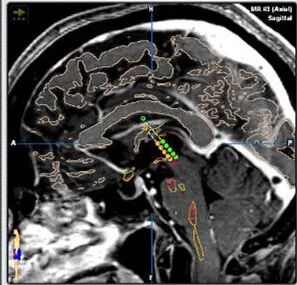

患者入院后,需要做相应的术前检查和术前各项评估。在手术前一天需要做头颅磁共振检查,以便根据影像学检查结果制定相应的手术导航计划。

手术当天给患者安装好头架后做CT检查。

整个手术,我们通过术前计划系统、术中微电极记录、患者术中的症状缓解和植入后复查的影像学资料,4个方面保证电极精确的植入在相应的核团上。